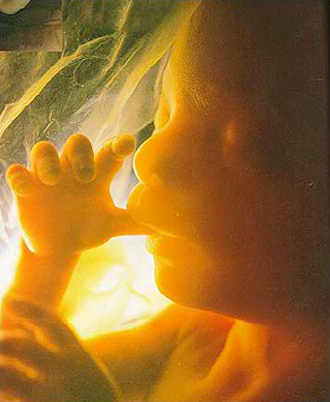

- 선택 검사 (16주~20주)

- 양수검사 (분만시 연령이 만 35세 이상, 기형 가족력이 있는 경우는 필수)

- 필수 검사

- 복부 초음파 (1회/4주)

- 중기 정밀 초음파

(태아 내부장기 및 근골격 기형 등을 검사)